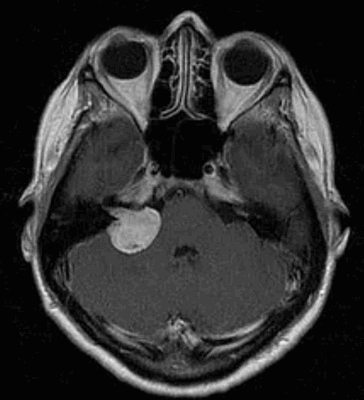

Наиболее информативным методом выявления вестибулярных шванном является МРТ головного мозга с контрастным усилением в режиме Т1 и Т2. Это исследование позволяет определить размеры опухоли, наличие перитуморозного отека, наличие признаков окклюзионной гидроцефалии, которая может быть следствием сдавления опухолью IV желудочка. Кроме этого МРТ позволяет провести дифференциальную диагностику с другими опухолями схожей локализации (чаще с менингиомой задней грани пирамиды височной кости). Еще одним стандартом диагностики является КТ в костном режиме. Независимо от снижения слуха стандартом является проведение аппаратной аудиографии.

Классификация KOOS

I стадия: опухоль находится в пределах внутреннего слухового прохода, диаметр экстраканальной части составляет 1-10 мм.

II стадия: опухоль вызывает расширение канала внутреннего слухового прохода, и выходит в мостомозжечковый угол, ее диаметр составляет, 11-20 мм.

III стадия: опухоль распространяется до ствола головного мозга без его компрессии, диаметр составляет 21 - 30 мм.

IV стадия: опухоль вызывает компрессию ствола головного мозга, ее диаметр более 30 мм.